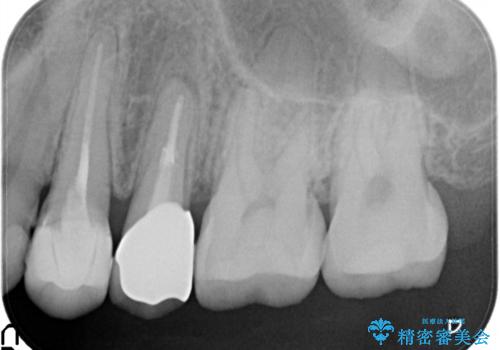

歯肉の中までの深い虫歯 部分矯正後のセラミック治療

歯を部分矯正で引き上げて、虫歯を徹底的に取り除き、適合の良いかぶせ物を装着する計画としました。